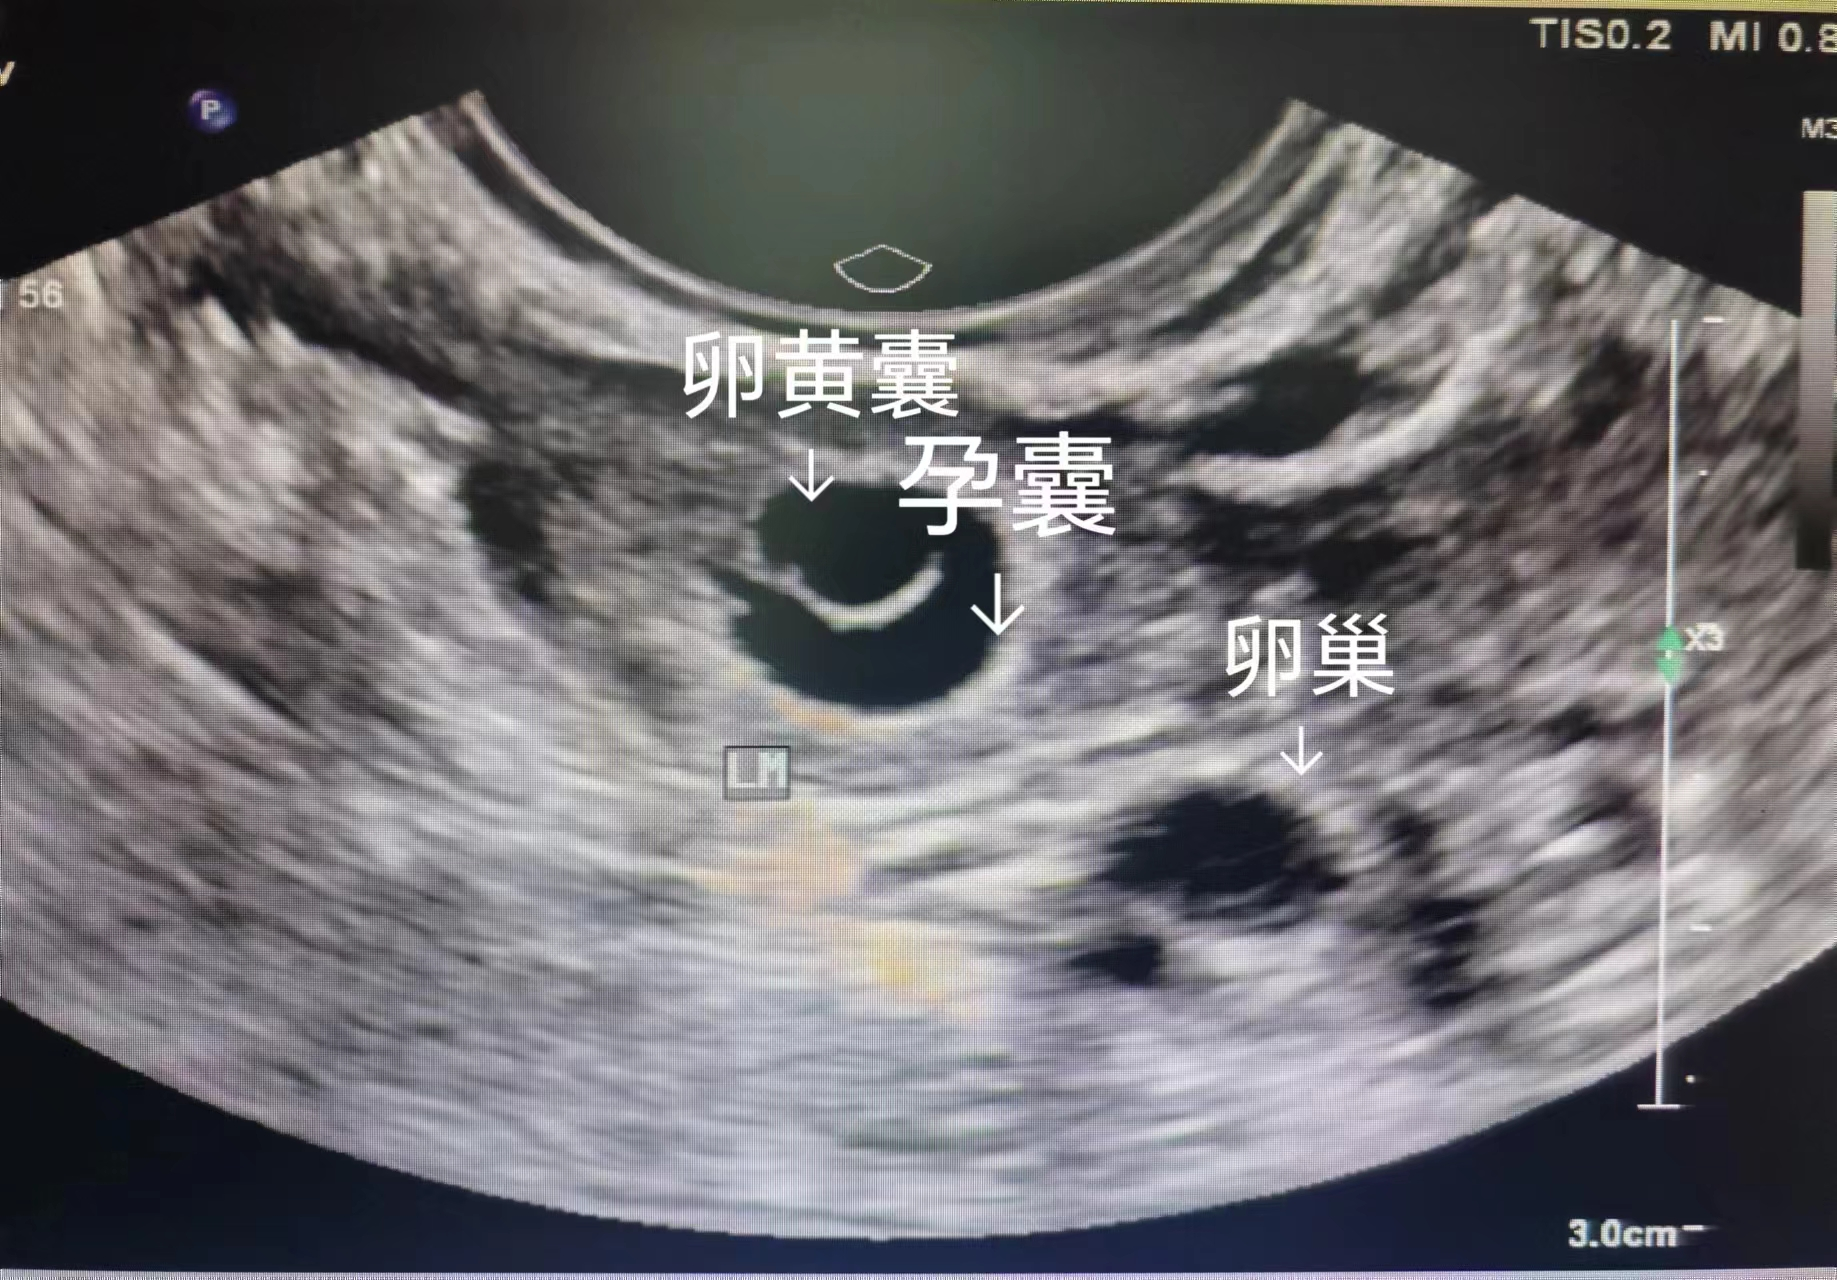

这是孕早期超声最核心的作用。通过超声可清晰看到孕囊位置,判断是否为宫内妊娠,及时排除宫外孕或葡萄胎等可能引发阴道大出血、恶变的异常妊娠)。

宫内正常妊娠